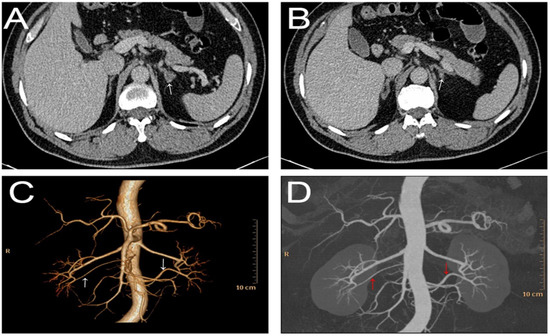

Figure 2.

Histopathologic pictures of left adrenal gland. (A) Hematoxylin–eosin staining for left adrenal gland; the blue oval showed the left adrenal adenoma; the blue rectangle part of gland in (A) was magnified as shown in (B). (B) Hematoxylin–eosin staining showed fasciculata (ZF)-like cells, which were large, lipid laden clear, with round to oval vesicular nuclei, and zona glomerulosa (ZG)-like cells, characterized as small, compact cells, with high nuclear/cytoplasmic ratio and moderate amount of lipid.